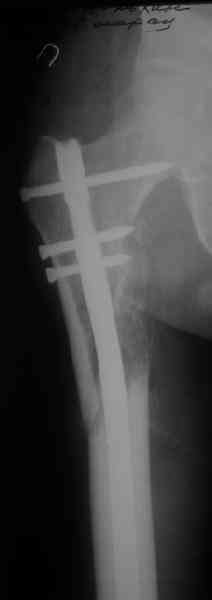

> денамизация - февраль 2006. ( 3 и 4 снимки) на сегодняшний день (снимок 5) беспокоит боли в тбс...

> Вот несколько. С тисками и трубой на днях сделаем.

Саша, последний штифт, пожалуй, перегнули?

Внимательно посмотрите на последний снимок. При казалось бы малом размере стержня, резорбции кости вокруг него не отмечается, что говорит о определенной стабильности его в костномозговом канале.

< Что он до сих пор не <раздавился> ?

А то и не раздавился - что проксимальный фрагмент < висит> на этом винте.

Безусловно, если рассматривать проблему глобально, с коррекцией длины конечности, подход должен быть другим. Но для достижения консолидации перелома думаю, что такой вариант приемлем.